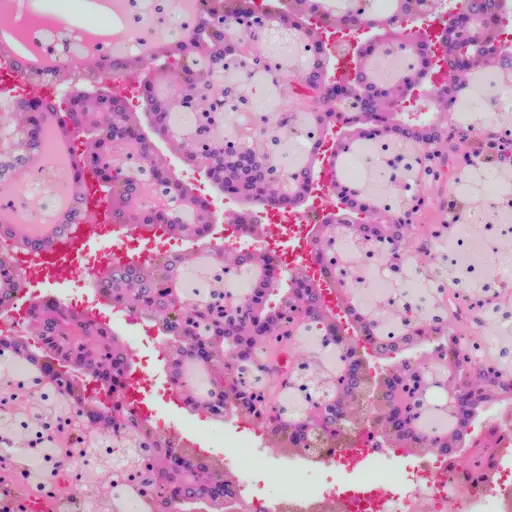

“肾癌有十多种亚型,”洛杉矶加州大学洛杉矶分校健康中心肾癌项目主任布莱恩·舒奇医学博士说。芝加哥大学医学助理教授、血液学家Randy F. Sweis医学博士说,最常见的是“透明细胞”,大约80%的肾癌都是由这种细胞引起的。这种亚型反映了癌症开始于哪个肾细胞,这有助于确定最佳的治疗方法。“一种肾癌亚型的治疗方法可能与另一种非常不同,”斯威斯博士说。

为了确定分期,如果肿瘤很小,可以进行简单的X射线;Shuch博士说,对于更具侵略性的肿瘤,可以完成先进的成像。“虽然在显微镜下检查来自肿瘤的活组织检查 - 通常为患者提供,但许多选择直接进行治疗(没有活组织检查),这取决于疾病程度和肿瘤对成像的外观,“添加Zabell博士。成像通常是CT或MRI,其用于评估肾脏以及腹部的其他部分以确定肿瘤是否已经扩散。